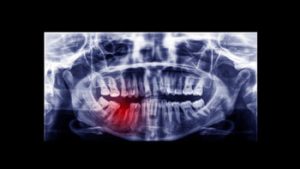

average number of root canals by age xrayWhy Regular Dental Care Makes the Difference

The key to managing root canal needs lies in consistent and proactive dental care. Professional cleanings remove bacteria that home care can miss, and regular exams detect small issues before they escalate. Root canal procedures are avoidable in many cases through timely intervention. If tooth pain becomes persistent or decay is visible, don’t wait for symptoms to worsen. Seeing a dentist early often leads to less invasive treatments and better outcomes.

The link between cavity development and root canals is well established. Once decay progresses past enamel and dentin, it often reaches the pulp, necessitating treatment. The average number of root canals is higher among patients who delay dental visits or skip check-ups. Waiting too long can mean the difference between a simple filling and a full procedure. Root canal therapy plays a vital role in protecting oral health by preserving the tooth and stopping the infection from spreading further. Early detection through exams and X-rays is essential to catch decay before it becomes irreversible.